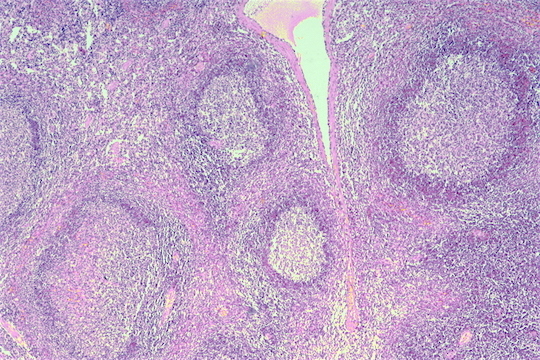

Here is the normal appearance of a benign reactive lymph node. Lymphatics that drain tissues peripheral to the node enter the subcapsular sinus and lymph percolates around and into lymphoid follicles of variable size and having a surrounding mantle zone that is surrounding a pale germinal center in which the immune responses are often generated with a predominance of B cells. Sinusoids extend to the center of the node.